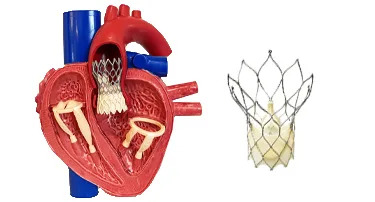

Innovative Heart Valve Solutions That Avoid Open-Heart Surgery

For decades, open-heart surgery was the sole method for repairing or replacing a defective heart valve. Although effective, the old method is marked by giant incisions, extended recovery periods, and jeopardy to elderly or high-risk patients.

TAVI Vs. Open-Heart Surgery: Which Is The Right Choice For You?

For heart valve replacement, patients usually have two primary choices: Transcatheter Aortic Valve Implantation (TAVI) and open-heart surgery. Both involve replacing a faulty aortic valve, but they are very different in approach, recovery period, and applicability to various patient populations. Knowing the main differences, advantages, disadvantages, and success rates can assist you in making an informed choice.

Who Is The Ideal Candidate For TAVI? Understanding Eligibility & Benefits

Transcatheter Aortic Valve Implantation (TAVI) has revolutionized the treatment of severe aortic stenosis, especially for patients who are high-risk candidates for traditional open-heart surgery. This minimally invasive procedure offers a lifeline to many, but determining who stands to benefit the most is crucial.